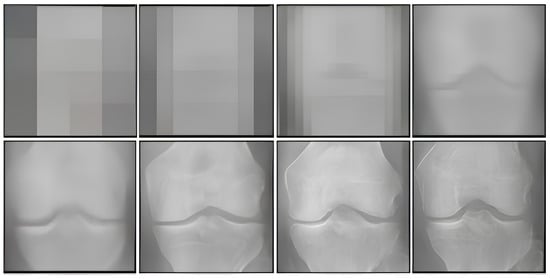

3.2. Image Generation Results: Qualitative Analysis of Image Artifacts

3.4. Training Dataset Size